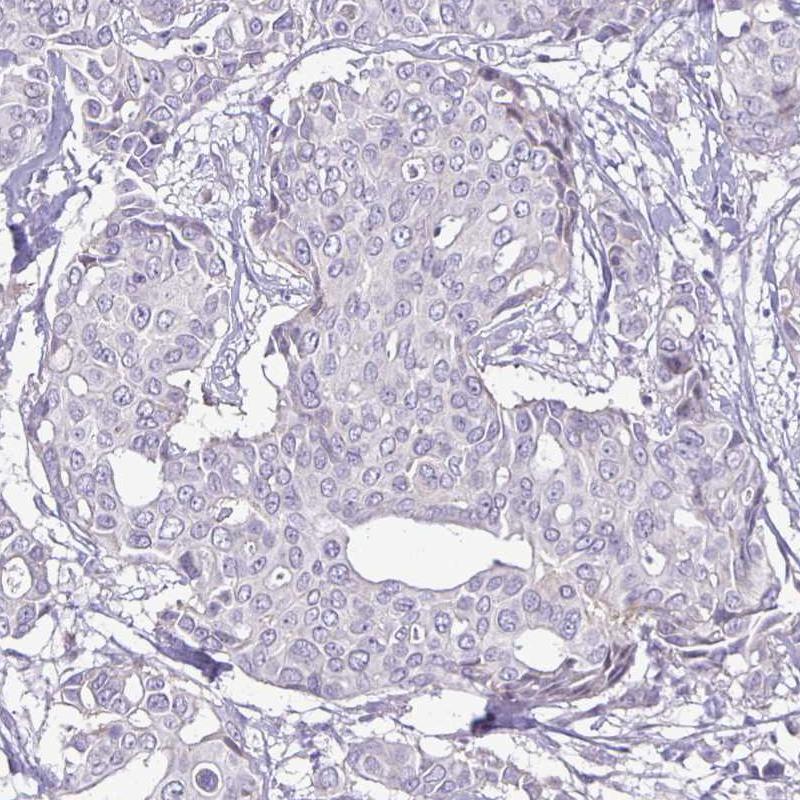

Immunohistochemical staining of human HER2-positive breast cancer shows strong membranous positivity in tumor cells.